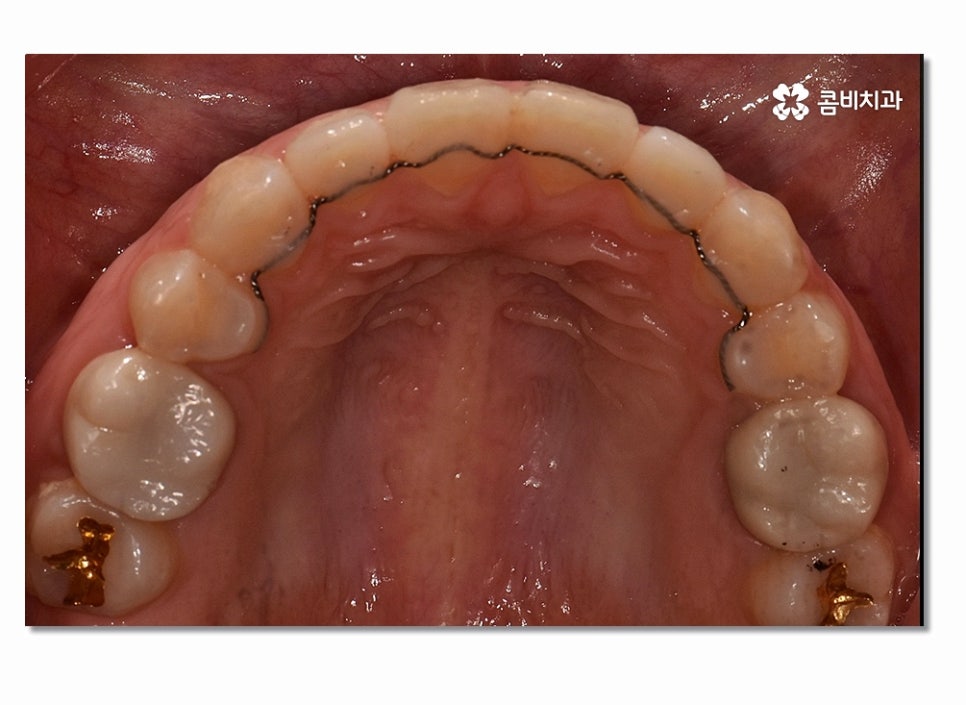

돌출입을 개선하기 위해서는 기본적으로 앞니의 각도와 배열, 위치 등의

조절이 필요하며 발치를 해야 하는 경우 보편적으로 송곳니 옆

작은 어금니를 발치하여 치아의 이동 공간을 확보하는 경우가 많다고 할 수 있어요.

치아교정을 위해서는 치아가 이동할 수 있는 공간이 충분히 확보되어야 하며

돌출입치아교정의 경우 치아가 전방으로 뻐드러진 상태를

후방으로 이동시켜야 하기 때문에 원하는 결과를 위해서 필요에 의해

발치가 진행되는 경우도 많다고 볼 수 있어요.

일반적으로 작은 어금니를 발치하게 되는 이유라면 전체적인

악궁 크기에 맞게 치아를 이동시킬 공간 확보의 의미가 크며

위 사진을 보시면 치아교정 과정을 통해서 치열의 가지런함은 물론이며

측면에서 보더라도 돌출입이 많이 개선된 것을 느낄 수 있을 거예요.